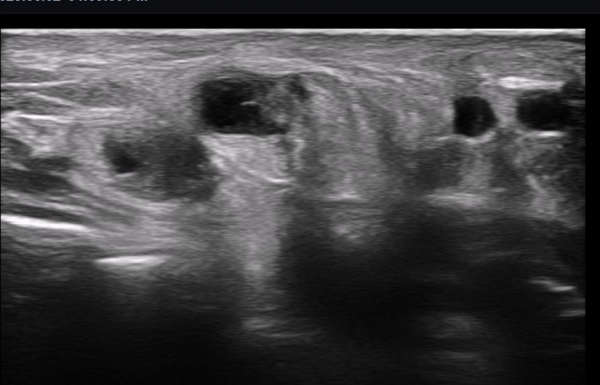

ÃÊÀ½ÆÄ ¼Ò°ß : ºñº¹½Å°æ Ⱦ´Ü¸é°Ë»ç¿¡¼­(»çÁø 1~13) ºñº¹½Å°æÀÇ Àú¿¡ÄÚ ºÎÁ¾°ú ´Üºñ°ñ°Ç³» ³¶Á¾¼º º´º¯ÀÌ °üÂûµÈ´Ù.

ºñº¹½Å°æ Á¾´Ü¸é°Ë»ç(»çÁø 14, 15)¿¡¼­ ºñº¹½Å°æÀÇ Àü¹ÝÀûÀÎ Àú¿¡ÄÚ ºÎÁ¾°ú ºñº¹½Å°æ ½ÉÃþÀ¸·Î ´Üºñ°ñ°Ç³»

³¶Á¾¼º º¯º¯ÀÌ °üÂûµÈ´Ù.